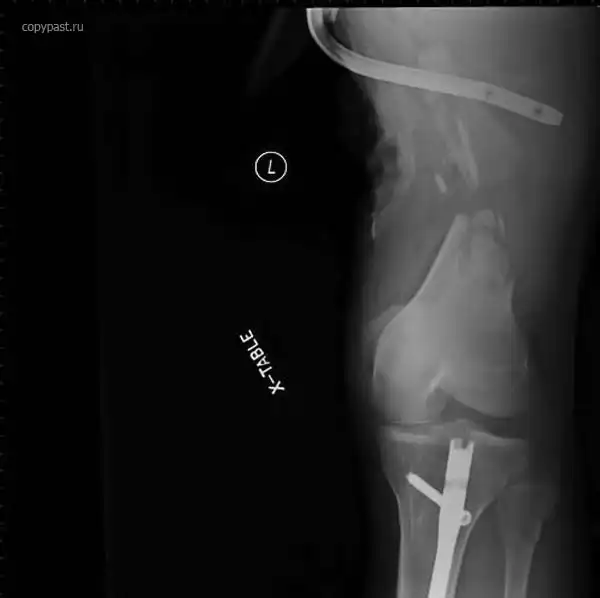

Человек сидел на переднем пассажирском сиденье в автомобиле, закинув ноги на торпеду,

в том месте, где находится подушка безопасности.

Произошла авария на скорости 40 км/ч, сработали подушки.... Вот так была сломана

ступня. Водитель не пострадал.

Я больше никогда туда не положу ноги